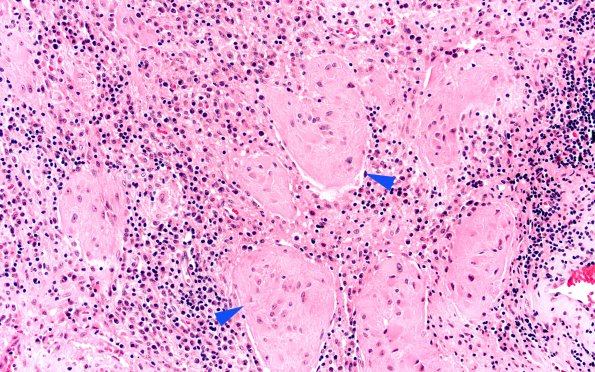

Washington University Experience | NEOPLASMS (NON-GLIAL NON-NEURONAL) | Germ Cell Neoplasm - Germinoma | 10A3 Germinoma, reaction (Case 10) Pineal H&E 20X copy

The border with the brain shows islands of gliotic parenchyma (arrowheads) surrounded by tumor and reaction (H&E)